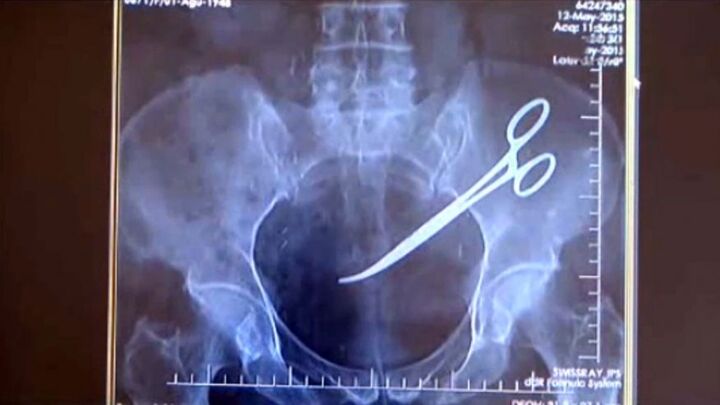

Một người phụ nữ Thổ Nhĩ Kỳ đã chịu đau đớn trong suốt 5 năm vì bác sĩ bỏ quên kéo trong bụng sau ca phẫu thuật tử cung.